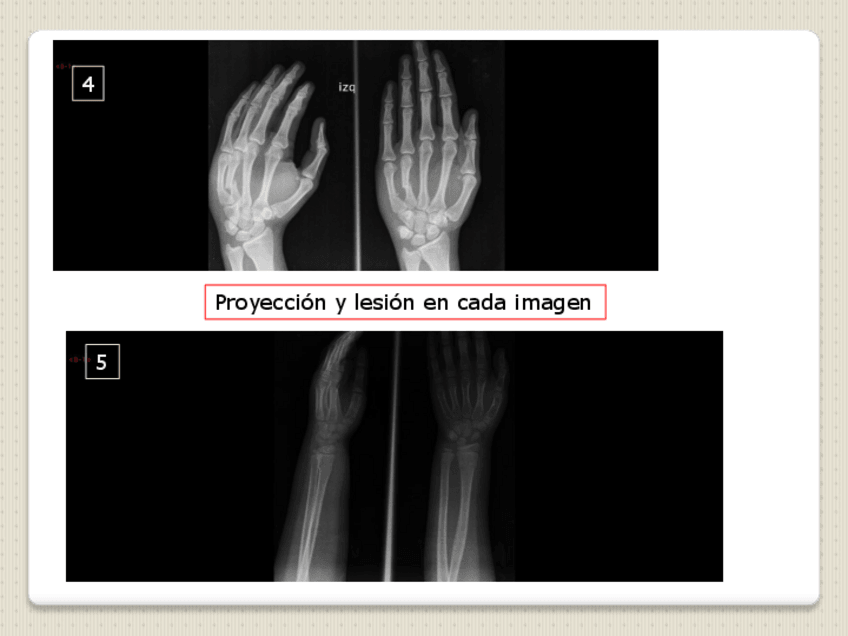

He publicado nuevos examenes de 2º Radiología en Fisioterapia: EXAMEN-RADIOLOGIA.pdf

He publicado nuevos examenes de 2º Radiología en Fisioterapia: SOLUCIONES-EXAMEN-MMSS.pdf

He publicado nuevos examenes de 2º Radiología en Fisioterapia: Examen-MMSS.pdf

He publicado nuevos examenes de 2º Radiología en Fisioterapia: MODELO-4-examen-EJERCICIO-PRACTICO-copia.pdf

He publicado nuevos examenes de 2º Radiología en Fisioterapia: MINIEXAMEN-MODELO-EJERCICIO-PRACTICO-copia.pdf